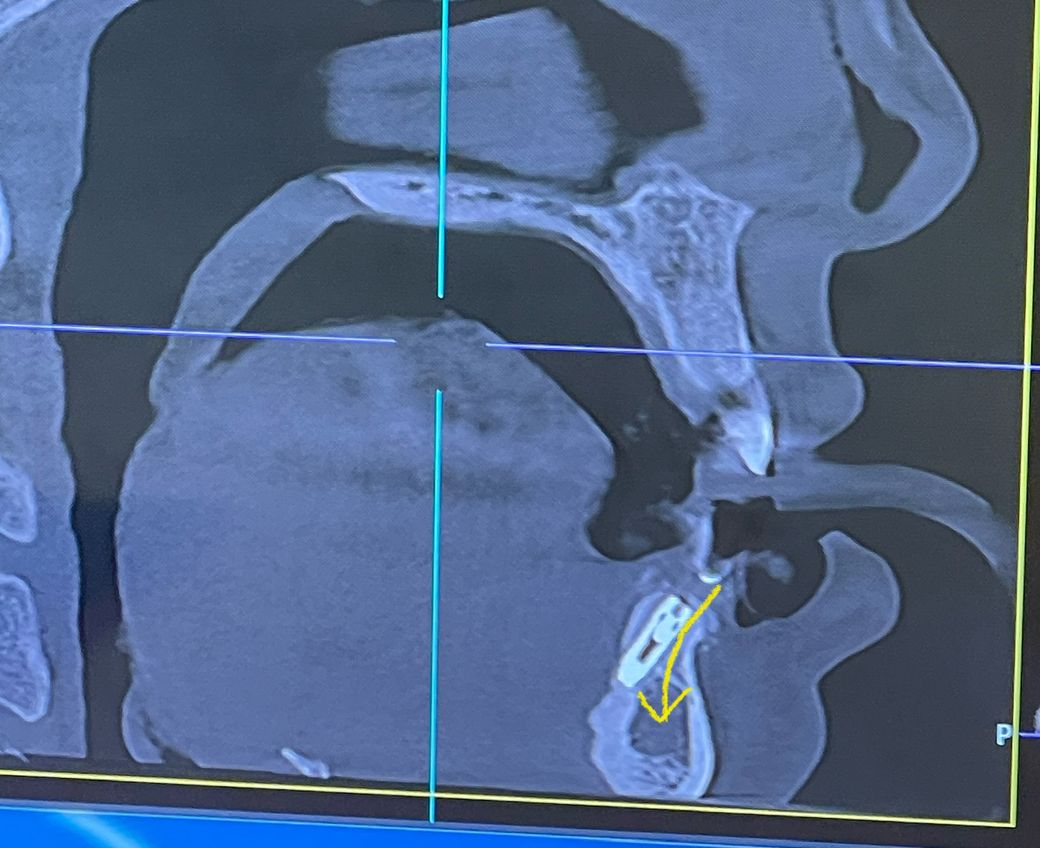

식립 각도 보다 위치가 이렇게 되도 맞는지 궁금합니다

@ 제가 궁금한건 저 동그란 턱벼 안에 해면골?? 안으로

들어가야 하지 않는가 와 이렇게 테두리뼈에 심어져도

쓰는데 문제가 없는지 궁금합니다.

식립각도는 문제될 것 없어보입니다. 씨티는 3차원 영상이므로 단면만 보고 판단하기에는 무리가 있습니다.

CT상으로 보면 저렇게 심어도 크게 상관은 없습니다. 오히려 표시하신 화살표 방향 아래쪽은 뼈가 물러서 그쪽을 피해서 심기도 합니다.

말씀하신 것처럼 임플란트 식립 각도는 해면골 내에, 잇몸뼈 중앙 부위로 정렬하는 것이 바람직하긴 하지만 케이스마다, 치과의사의 치료계획에 따라 식립각도는 다소 다를 수도 있습니다.